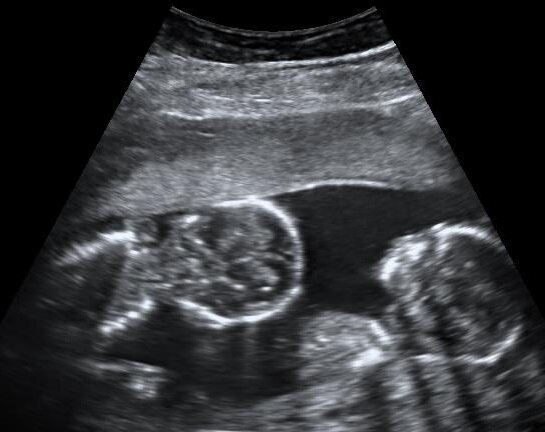

Как известно, существует две разновидности близнецов - однояйцевые и разнояйцевые. Первые получаются из одной зиготы, поэтому являются клонами друг друга, а значит, у них всегда один отец.

Разнояйцевые близнецы получаются из разных зигот. Это случается тогда, когда у женщины за один овуляционный период созревает две и более яйцеклетки. При этом каждая из них должна быть оплодотворена своим сперматозоидом.